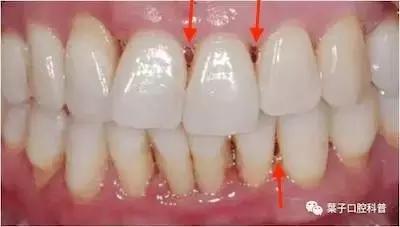

如果两颗牙齿之间的牙龈乳头退缩(牙龈萎缩),就会造成两颗牙齿之间下方出现空隙,食物就比较容易在嘴唇、脸颊和舌头的运动作用下,水平地进入了间隙,造成了“卡肉”的现象。

牙龈萎缩,需要考虑系统的牙周治疗或手术。